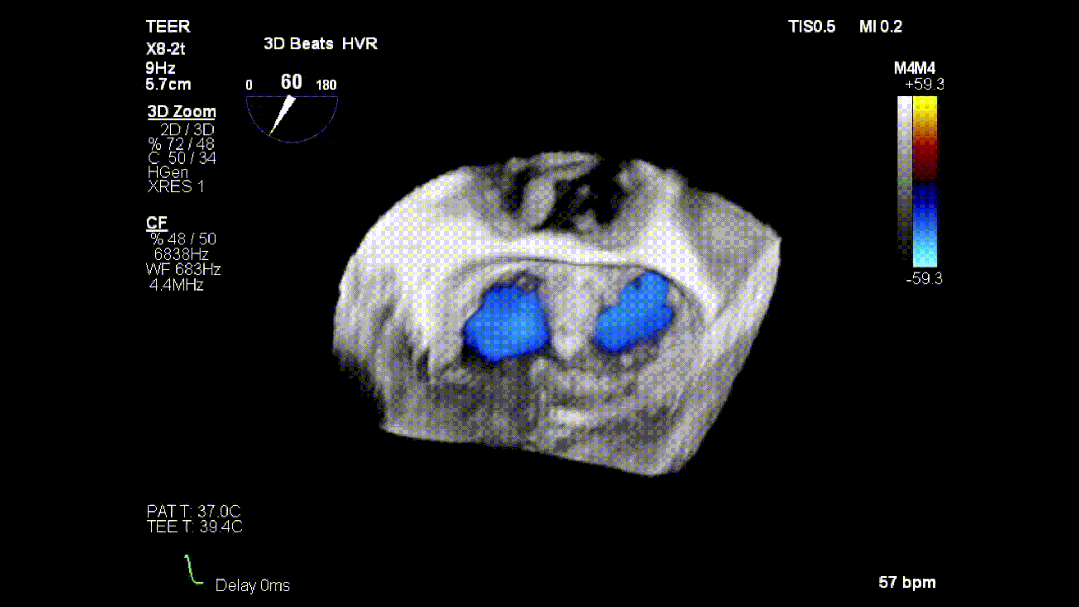

本次培训的“重头戏”—— 两台高难度 TEER 手术沉浸式观摩,将培训氛围推向高潮。手术病例分别为 “P2 宽大脱垂病变” 与 “早期 Barlow 病变”,由厦门大学心血管病医院团队与浙江大学附属邵逸夫医院团队协同完成。术中,专家团队操作精准、配合默契,不仅完美展现了 TEER 技术在复杂病例中的应用优势,更通过实时讲解,让学员直观掌握手术关键步骤、解剖评估要点与应急处理思路。

病例1: